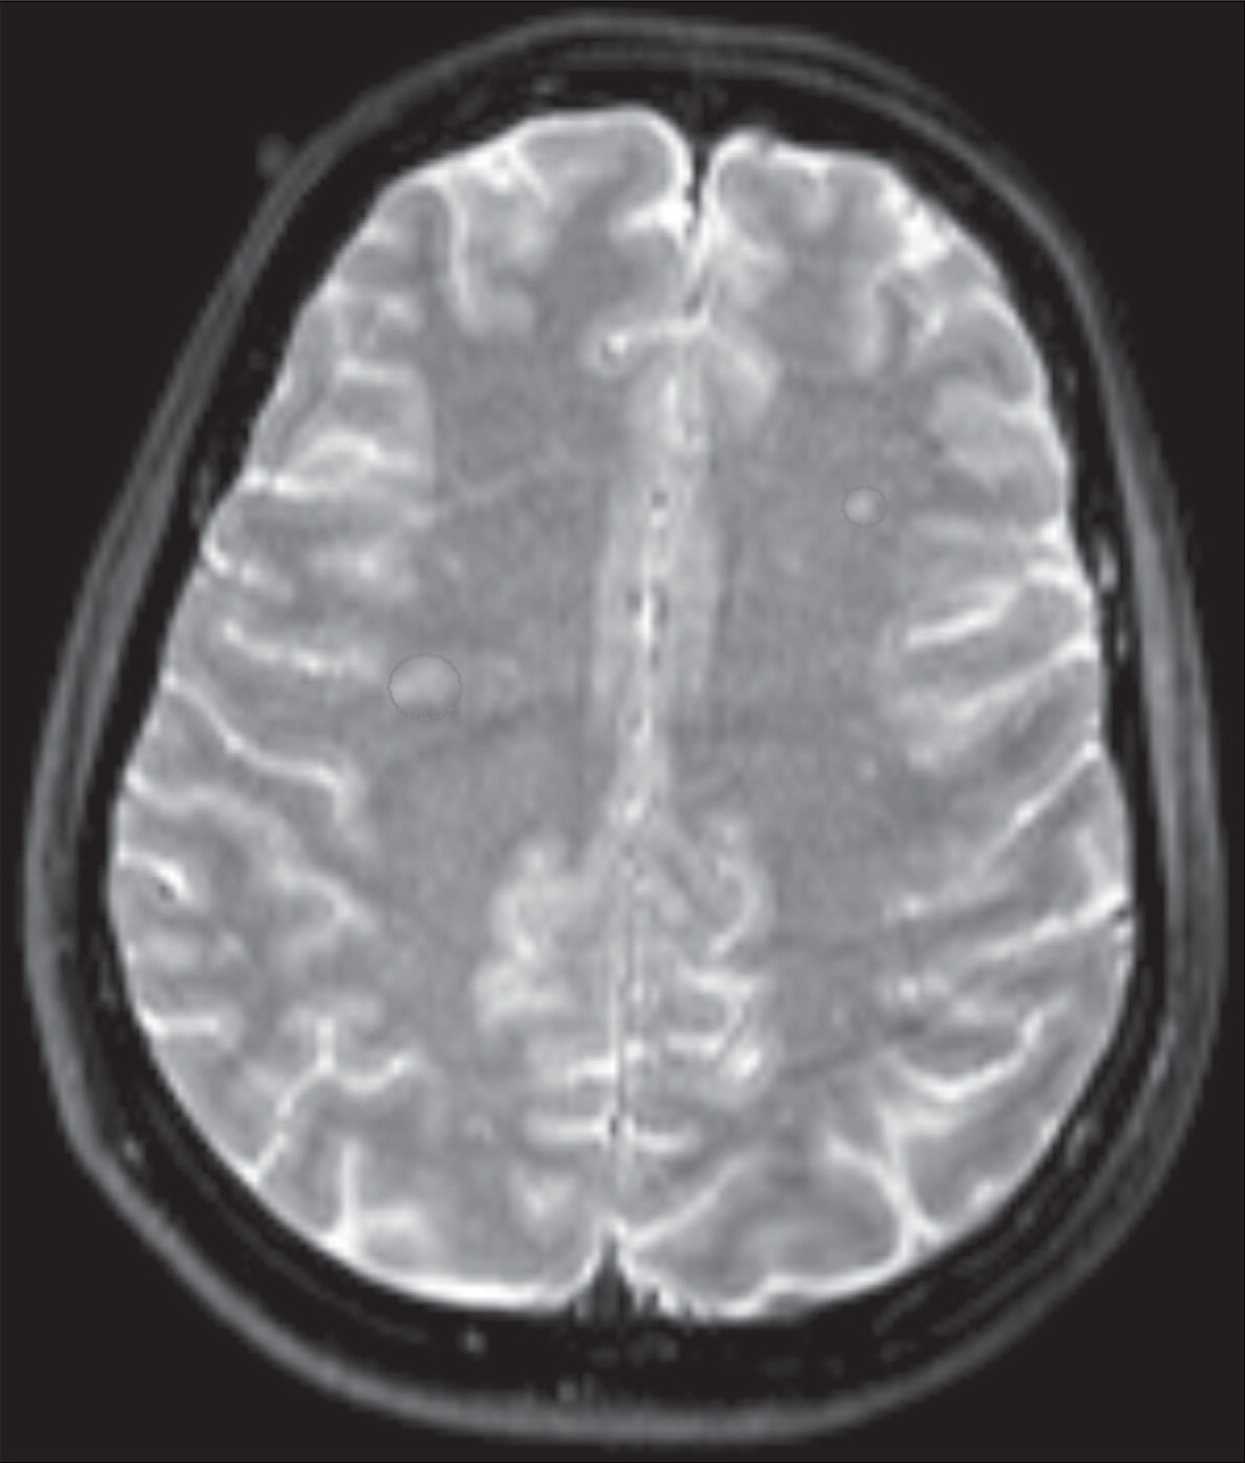

Врачи обследовали пациентку и провели ей электроэнцефалограмму. Результаты оказались нормальными, но магнитно-резонансная томография головного мозга показала несколько изменений в белом веществе вблизи чечевицеобразного ядра (lentiform nucleus) и в полуовальном центре (semioval centre). Эти поражения могли быть вызваны разрывами мелких кровеносных сосудов головного мозга. Согласно отчету врачей, ущерб был нанесен достаточно давно.

Хотя электроэнцефалограмма не выявила отклонений, врачи подозревали, что зрительные галлюцинации были вызваны аномальной электрофизиологической активностью в частях мозга, которые обрабатывают цвета и лица, в частности в вентральной затылочно-височной коре. Эта область, расположенная в задней части мозга, регулирует распознавание объектов. По мнению врачей, поражения мозга, выявленные с помощью магнитно-резонансной томографии, могли вызвать эту активность. Возможно, такое состояние было у нее с рождения. Его могло вызвать временное лишение кислорода незадолго до или после родов.